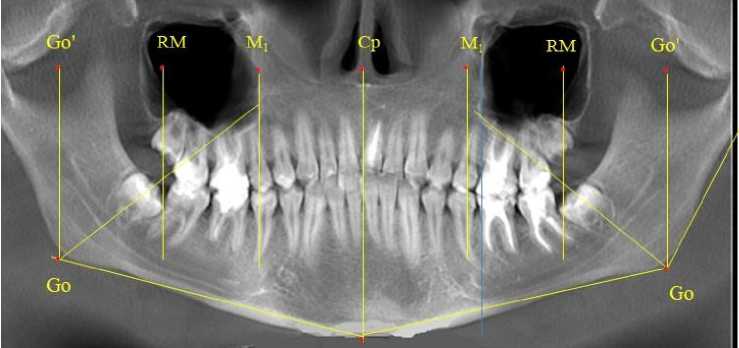

Особенностью исследуемого возрастного периода было то, что зачатки вторых верхних постоянных моляров располагались впереди ретромолярной вертикали. Данное обстоятельство свидетельствовало о благоприятном расположении зачатков, что в последующем обеспечивало их прорезывание по мере формирования корней. Кроме того, указанный размер (Ср-RM) определял зубоальвеолярный размер верхней челюсти (правой и левой). Молярная вертикаль исходящая из молярной токи (М1), в отличие от периода молочного прикуса, смещалась к средней трети медиальной поверхности вторых молочных моляров обеих челюстей, что связано увеличением ретромолярной области (рис. 5).

Рис. 5. Ортопантомограмма ребенка 7 лет после прорезывания первой группы постоянных зубов

Зачатки вторых постоянных моляров нижней челюсти располагались кпереди по отношению к биссектрисе угла Go´-Go-Ме, что так же, как и на верхней челюсти, оказывало благоприятное влияние на формирование и прорезывание нижнего первого моляра. При анализе боковых телерентгенограмм и трехмерной модели установлено, что положение зубов и челюстей относительно реперных линий было близким по значениям, полученным при анализе ортопантомограмм. Биссектриса угла Cond-Go-Ме, так же, как и на ортопантомограмме, располагались позади от формирующихся зачатков вторых постоянных моляров нижней челюсти (рис. 6).

Данное обстоятельство свидетельствовало о благоприятном расположении зачатков. Молярная вертикаль, исходящая из молярной токи ( М 1 ) проходила вблизи средней части коронок вторых молочных моляров обеих челюстей (рис. 7).

Рис. 7. Ортопантомограмма ребенка 8 лет после прорезывания постоянных резцов